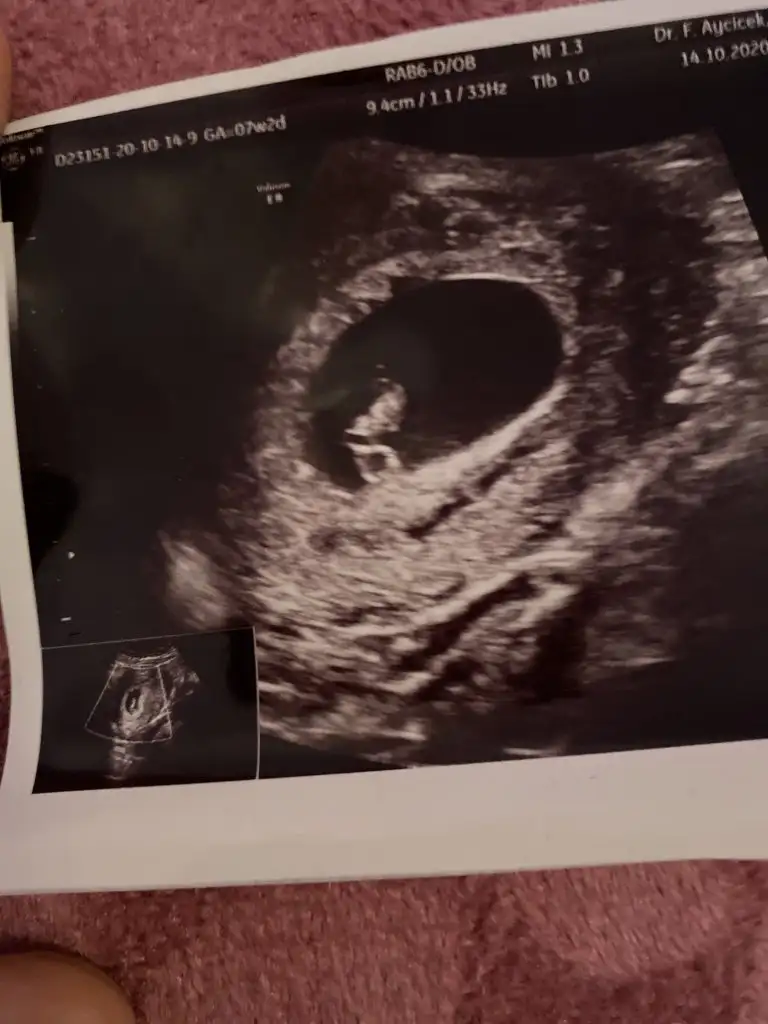

Canım 9 haftalıkken neden vajinal ultrason yaptı ki ?Bana tahminde bulunabilecek var mı bu ultrason 9 haftalıkken vajinal ultrason

Erkek bencrBana tahminde bulunabilecek var mı bu ultrason 9 haftalıkken vajinal ultrason

Karindan ve 7+0Kaç haftalık karında sa kız vajinalse erkek

Kız gibi ama bu teori tutmayan cok öğrenin ce yazarsınKarindan ve 7+0